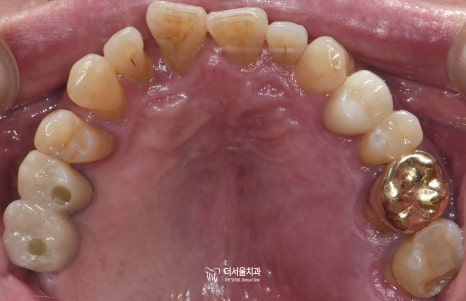

『최종 결과』

이렇게 당뇨 환자분 임플란트 수술은

뼈이식까지 잘되며 마무리되었습니다.

아직은 뼈와 조금 더 결합이 이뤄져

튼튼한 고정이 이뤄져야 되기에

당분간 조심히 쓰셔야 된다는

유의 사항을 알려드렸습니다.

또, 알려드린 대로

주기에 맞춰 검진을 꼭 받으러 오실 것을

약속받으며 해당 치료를 끝마쳤습니다.